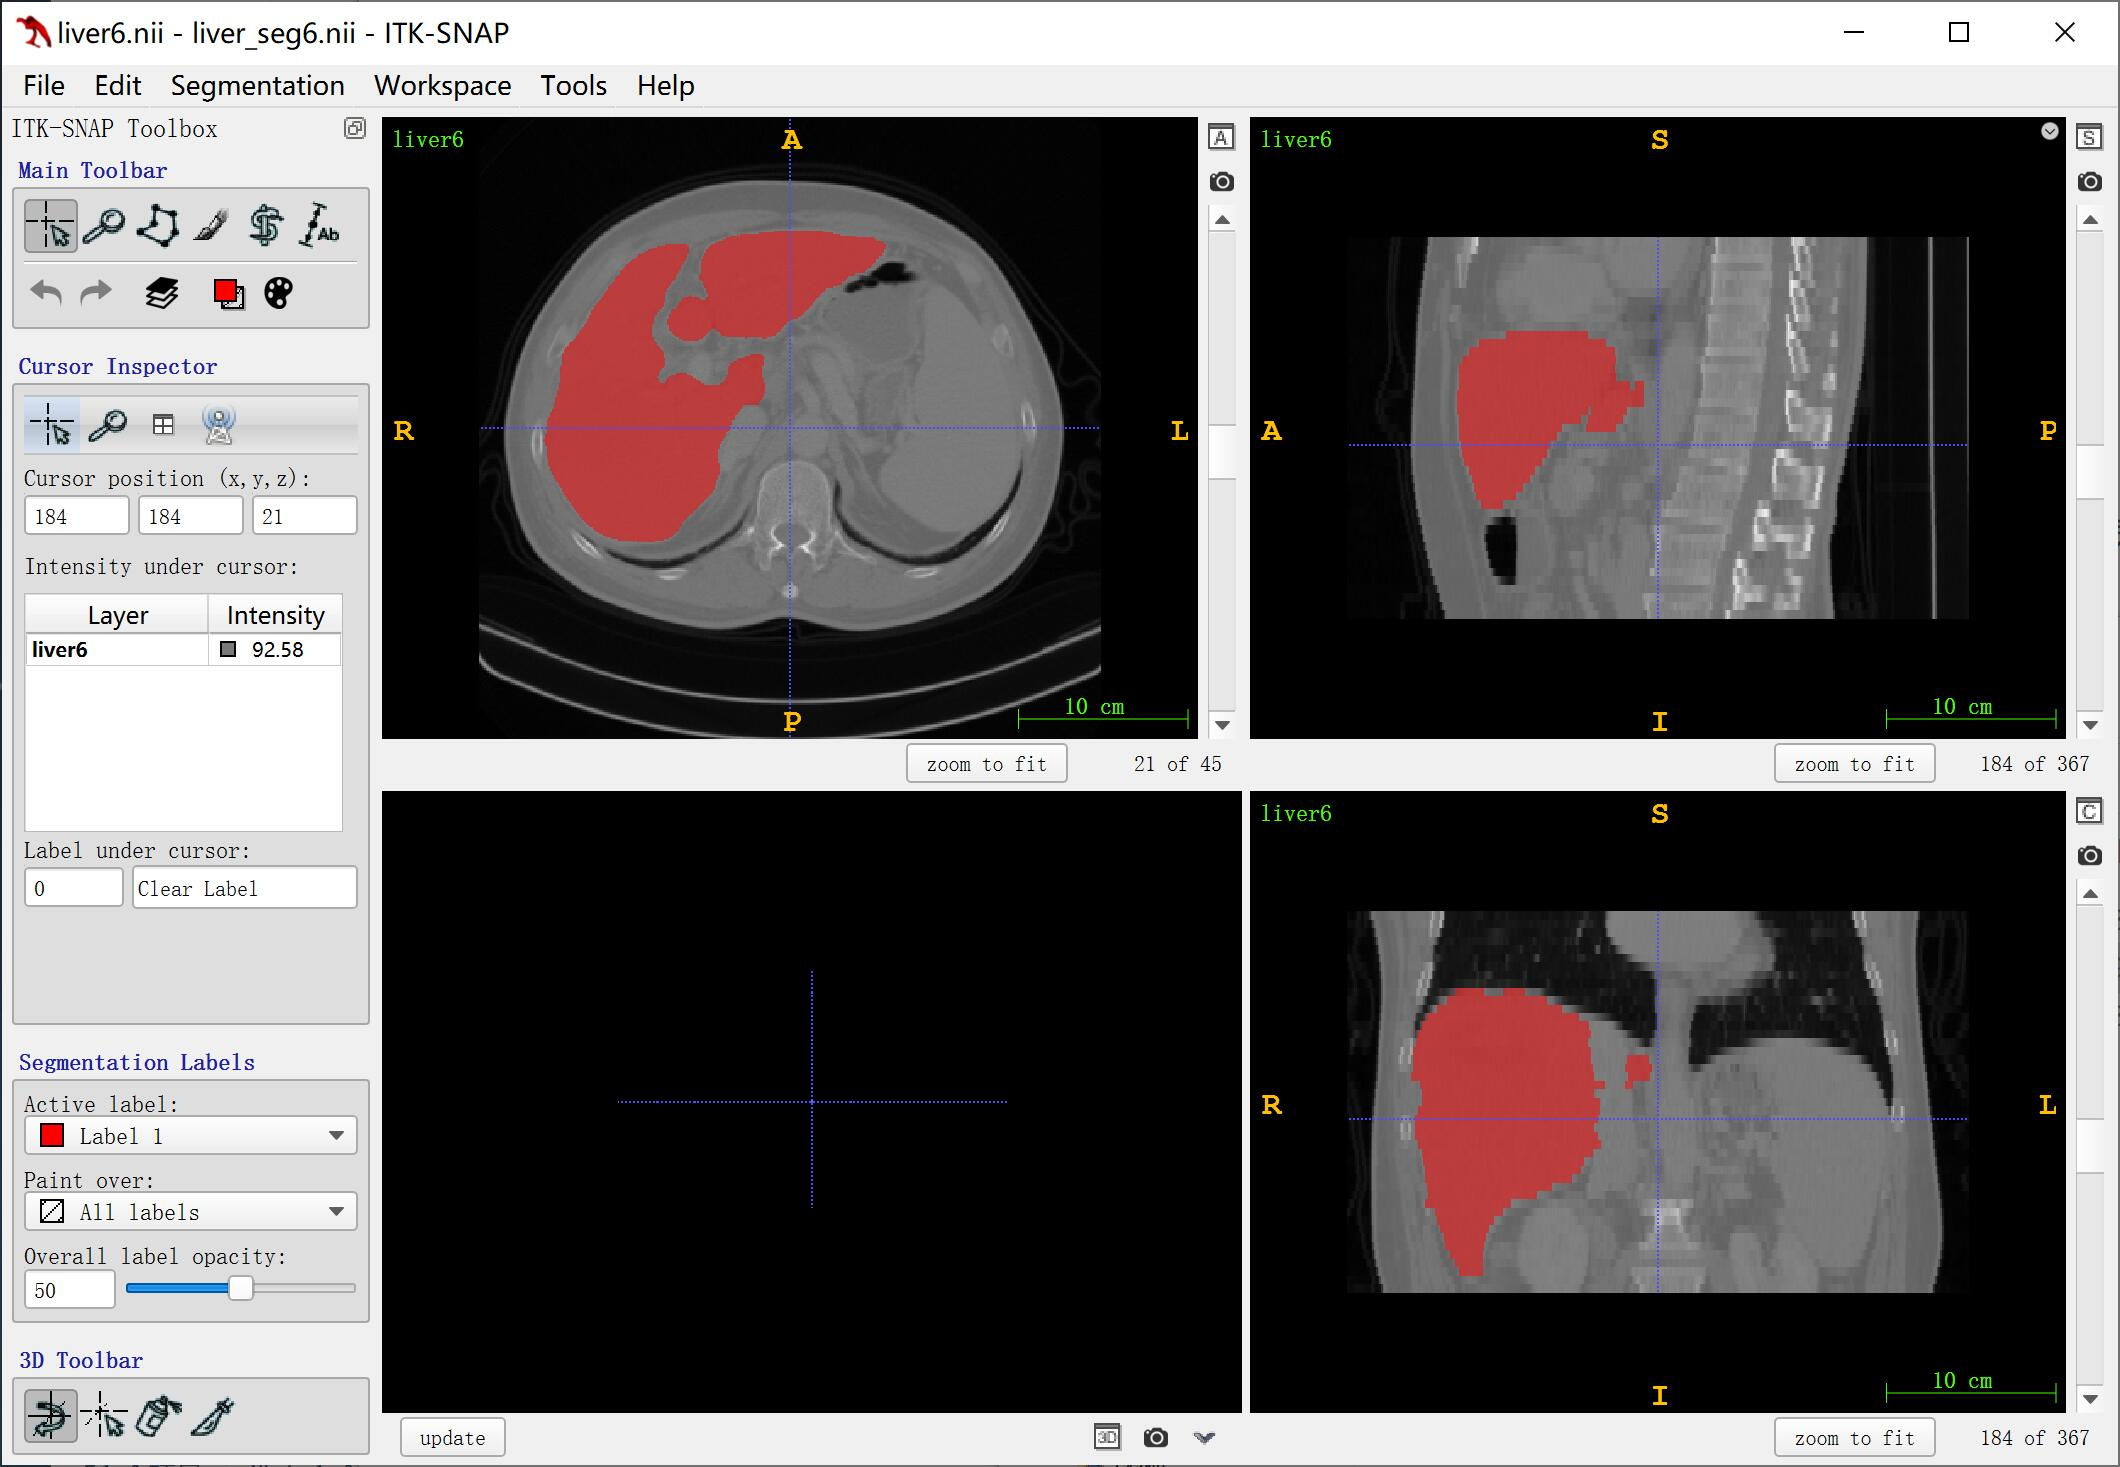

1. ITK-SNAP 软件

安装之后在打开 .nii 格式的文件时直接选择该软件即可,如上图所示,该软件可以显示在 x、y、z 三个轴方向上的视角,并且可以进行调整。如果不仅想要展示医学图像本身,还要展示对应的分割结果,则可以把分割结果的 .nii 文件直接拖入软件窗口中,并选择以分割的形式载入即可。但是据我目前的使用来说,好像不能同时载入多个分割结果(比如一个器官本身的分割,一个肿瘤部位的分割)。